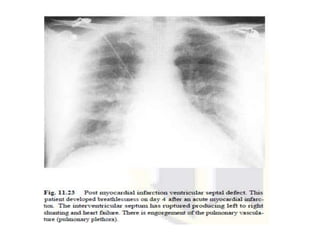

Rupture of the interventricular

septum

• Most likely to rupture between 4 and 21 days

postinfarction rapid-onset left to right shunting

and heart failure.

• rare complication, occurs in up to 2% of all acute

cases

• Engorgement of the pulmonary vasculature

(pulmonary plethora) and pulmonary edema

frequently seen.

• The definitive diagnosis is clinical and

echocardiographic.